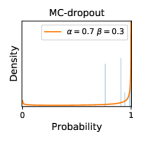

5.1 Distribution of Uncertainty Scores

Distribution of Uncertainty Scores Across Different Severity Levels As explained in Section 3, each uncertainty metric essentially defines an order/ranking among the data points. We conducted an analysis to better understand what data will be assigned high uncertainty under a particular uncertainty metric . Picking out the highest ranked data points (), we calculated the ratio of data points from each SL. Figure 4 summarizes the results as box plots for the Kaggle-DR and the Messidor-2 datasets; additional detailed statistics can be found in Table S.1 in the supplementary materials. From the plot and table, SL1 & SL2 examples account for a higher proportion among the top-ranked uncertain examples across the three ensemble methods. This finding matches our intuition that incipient disease examples (SL1 & SL2) are more likely to be considered uncertain by ensemble methods due to their ambiguity.

Comparing the three ensemble methods in Figure 4, the stacking ensemble method has the highest ratios of SL1 & SL2 data among the high-uncertainty examples it identified under both mean and var. TTA showed slightly better performance than MC-dropout but still falls behind the stacking ensemble method. Considering the fact that SL0 examples accounted for the majority of the dataset, the stacking ensemble method was much more precise (specific) in selecting truly ambiguous data points that were difficult to classify. From Figure 3, we can also see that the stacking ensemble method greatly outperformed the other two methods in finding false negatives under both mean and var uncertainty metrics.

In contrast, the MC-dropout method showed the worst overall performance among the three, as it can be seen from the high ratios of SL0 examples among the uncertain negatives in Figure 4. The histograms in Figure 2 provides another perspective to look into the phenomenon, where a decent proportion of MC-dropout model’s predictions on SL0 inputs entailed low confidence (far from 0 or 1), which from another angle explained why MC-dropout was less specific in terms of lower FNP; many no-DR inputs (i.e. SL0) were erroneously assigned high uncertainty by MC-dropout models.

It is still an open question why the evaluated MC-dropout networks signaled relatively high uncertainty on SL0 & SL3 & SL4 data that are less likely to be ambiguous. We conjecture that much of the “uncertainty” indicated by disagreement among test-time dropout samples actually reflects the stochastic nature of dropout networks rather than the real decision uncertainty associated with the data. It is worth noting that the MC-dropout model we evaluated was not weak per se; they all achieved above Area Under Curve (AUC) scores on test sets. The weakness of individual test-time samples (which explains their low-confidence predictions on SL0 & SL3 & SL4) might have been hidden when they are aggregated into an ensemble—a well-known advantage of ensemble learning. Our results suggested that the uncertainty information given by implicit ensemble methods such as MC-dropout and TTA might not be as reliable as that from explicit ensemble approaches (e.g., stacking ensembles). Similar findings on MC-dropout can be found in some previous papers [1].